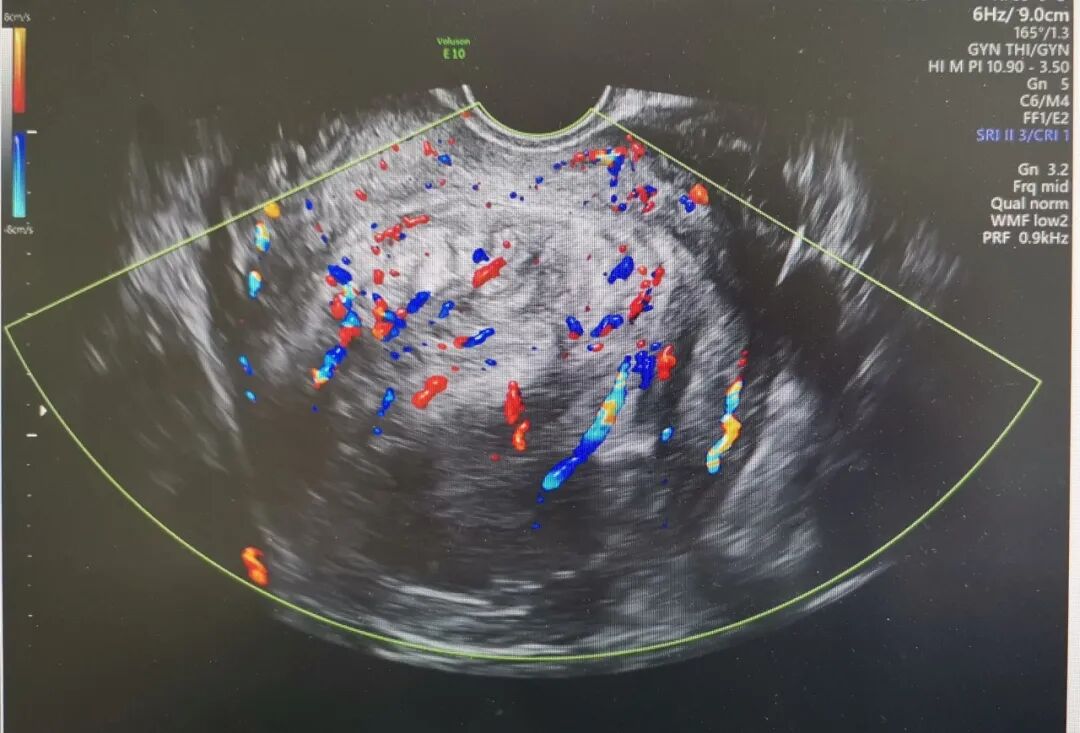

夏教授为患者安排了三维超声和宫腔镜检查,结果显示肌瘤位于宫底后壁,2-5型贯穿整个肌层,直径95mm,周边血流丰富。如果选择腹腔镜手术剔除肌瘤,子宫肌层完整性受到破坏,存在瘢痕子宫妊娠子宫破裂风险,宫腔镜手术创伤更小恢复更快,患者有生育计划,如果能通过宫腔镜手术治疗,是对生育功能最大的保护。但巨大的肌瘤马上手术,风险太大。夏教授决定先予GnRH-a类药物治疗手术预处理,缩小肌瘤体积,改善贫血后择期手术。4个月治疗后,血色素正常,宫腔镜检查显示肌瘤继续向宫腔突入,但仅稍微缩小至直径88mm,这对于宫腔镜手术仍然是个挑战。从“手术安全是第一位”的角度出发,夏恩兰主任和彭雪冰主任决定腹腔镜监护下进行宫腔镜手术,根据术中情况随时调整手术方式,“进可攻,退可守”。